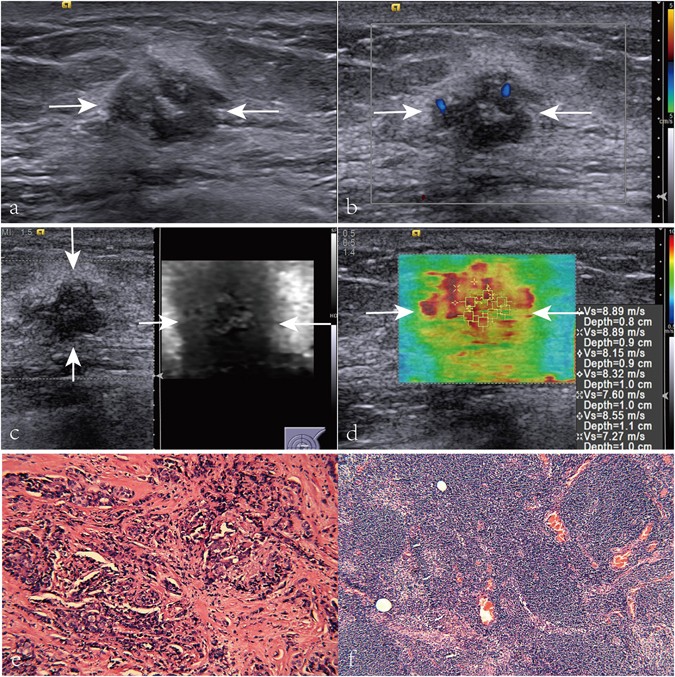

Images in a 58-year-old patient with breast invasive ductal carcinoma, axillary lymph node metastasis (LNM), histologic grade III, negative estrogen receptor (ER), negative progesterone receptor (PR), and positive C-erbB-2. (a) A solid, marked hypoechogenicity, well defined margin, irregular, and taller than wide shape lesion (arrows) is shown on US. (b) Rich internal flow (i.e. 3 linear or tree-like signals) is found on color Doppler flow image (arrows) of the breast invasive ductal carcinoma. (c) Virtual touch tissue imaging (VTI) score of the lesion (arrows) is 4. (d) On virtual touch tissue imaging & quantification image, the lesion (arrows) is heterogeneous with a mean SWS value of 4.75 m/s. (e) Pathological examination confirms the diagnosis of invasive ductal carcinoma (Hematoxylin-eosin stain, ×200). (f) Pathological examination confirms the diagnosis of axillary LNM (Hematoxylin-eosin stain, ×200).